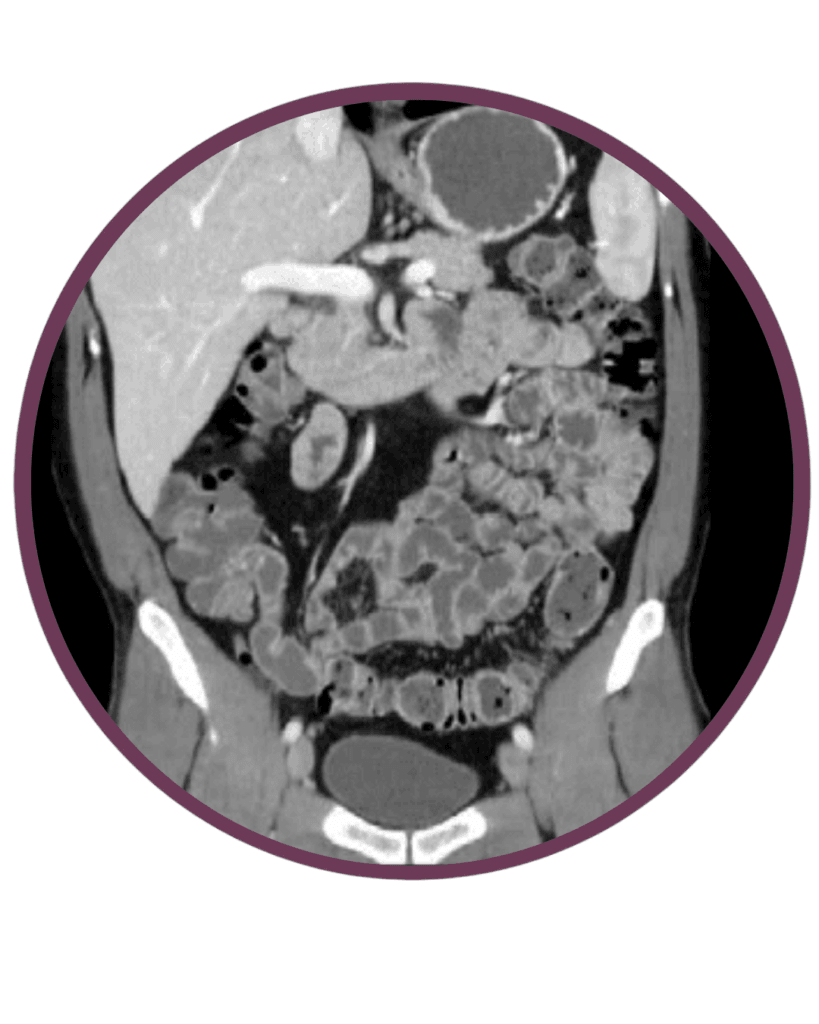

Vékonybél és vastagbél CT

Mi a vizsgálat lényege?

A vékony és a vastagbél CT vizsgálat egy speciális protokollal kivitelezett kontrasztos has és kismedence CT vizsgálat. Ennek során a beteg hashajtó adását illetve béltisztítást követően kevés kontrasztanyagot és nagy mennyiségú tiszta vizet iszik, mely kitölti a vékony és vastagbeleket, és ezáltal kimutathatóvá teszi a kóros bélfal megvastagodásokat, szűkületeket és egyéb stukturális eltéréseket.

Milyen előkészület szükséges?

A CT vizsgálat előtt fontos a kezelőorvossal történő konzultáció, hisz csak ez alapján dönthető el, hogy melyik protokollt alkalmazzuk. Ez a CT vizsgálat különleges előkészítést igényel, melyről a páciens a vizsgálat előtti napokban tájékoztatást kap.

Hogyan végezzük a vizsgálatot?

A vékonybél és vastagbél CT vizsgálat előtti napon béltisztítás elvégzése szükséges azért, hogy a bélben visszamarad bélsár ne zavarja meg a vizsgálat pontosságát. Emellett a vékonybél CT vizsgálat napján további kontrasztanyag illetve folyadék itatása és hashajtó adása is szükséges. CT-készülékünk egy nagy, vastag gyűrűhöz hasonlít, melynek aljában egy asztal van, ami mozog. Ön ezen az asztalon fekszik mozdulatlanul, miközben a felvételeket készítünk.